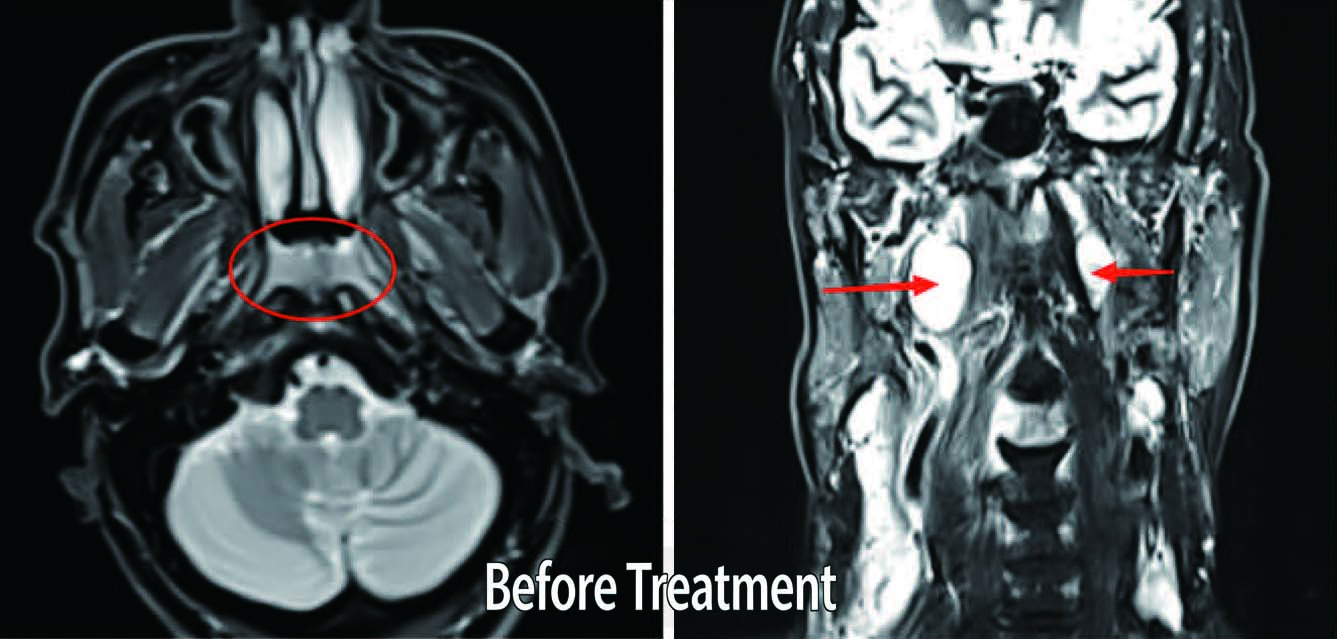

Patient: Male, 55 years old

Diagnosis: Nasopharyngeal Malignant Tumor {Undifferentiated Non-keratinizing Carcinoma)

Symptoms: Neck discomfort, primarily pain

P「escribed Dose:

PGTVnx: 70.29 Gy in 33 fractions (2.13 Gy per fraction) PGTVnd: 67.98 Gy in 33 fractions (2.06 Gy per fraction)

PTVl: 62.04 Gy in 33 fractions (1.88 Gy per fraction) PTV2: 54.12 Gy in 33 fractions {1.64 Gy per fraction)

Outcome:Eight months after treatment, follow-up MR imaging indicated a reduction in the size of the nasopharyngeal mass and positive lymph nodes compared to previous scans. Improvement in nasopharyngeal mucosal thickening was also observed.